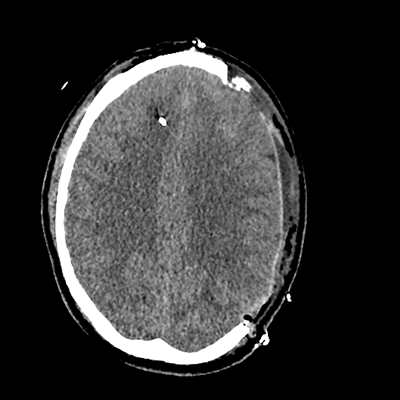

On day 5 of admission, he begins having intracranial hypertension again, spiking up to 40mmHg. You bolus with propofol and fentanyl, to no avail. You then push 30mL of 23.4% NaCl, which provides some brief improvement, allowing you to quickly get a non-contrast head CT. Unfortunately, he's now back up to 36mmHg. You review his labs, and note the following: Na 150, K 3.8, Cl 119, HCO3 18, BUN 21, Cr 0.85, glucose 136, sOsm 320.

NCHCT

NCHCT 5/20 5/20

NCHCT 6/20 6/20